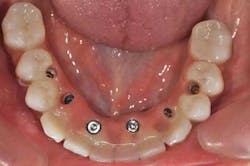

Fig. 7b: The positioning of the transfer copings already shows inadequate implant positions

Fig. 7c: Transfer coping placement on site 26 is impossible: this implant will have to be removed or submerged